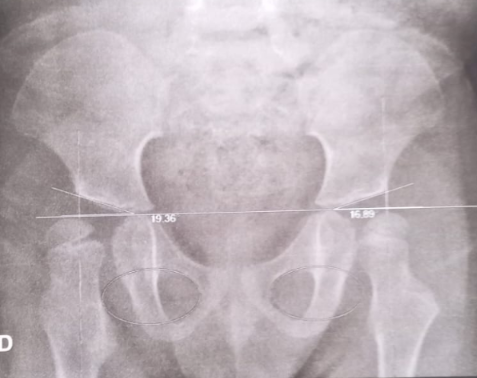

Ola me chamo Gabriel duarte de luca ,nasci com Síndrome de down ,vou fazer 4 aninhos e não ando ainda porque descobri que nasci com um problema na bacia chamado Hemiepifisiodese de fêmur proximal ,tenho que fazer uma cirurgia com urgência para colocar parafusos para que um dia eu possa andar não tenho condições pra fazer essa cirurgia conto com a ajudas de todos que possam me ajudar com qualquer valor